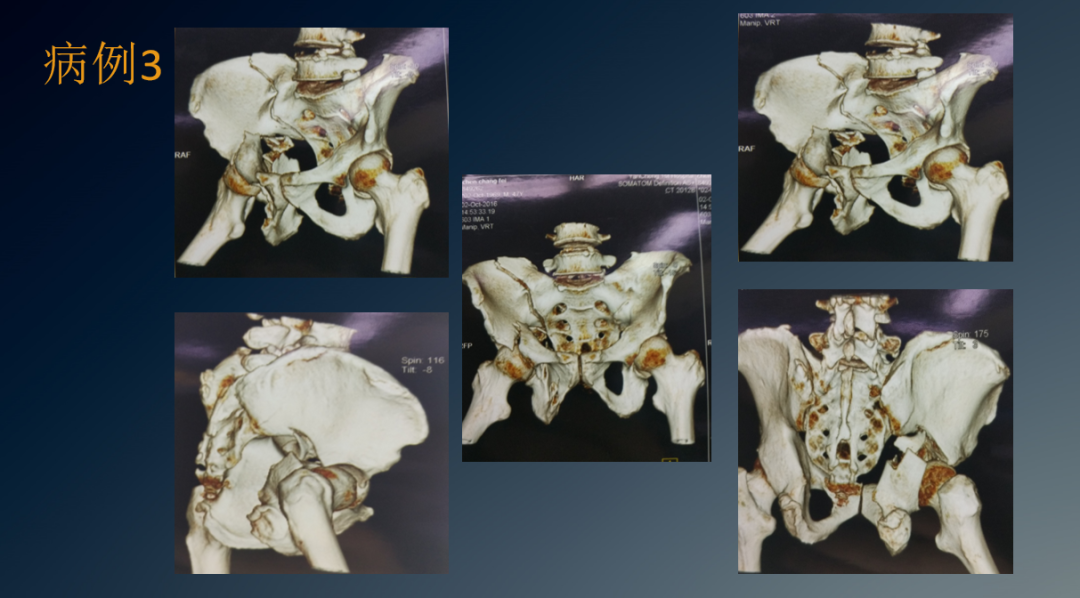

临床病例